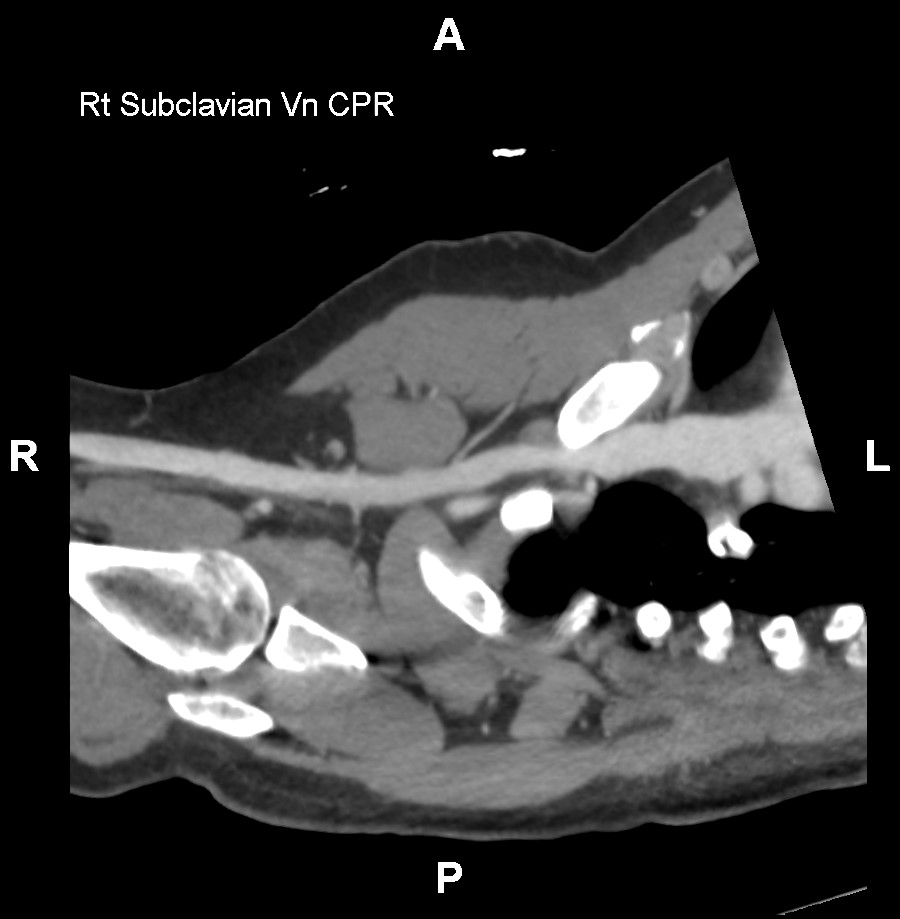

Our Venogram Service utilizes CT venography to offer a comprehensive view of the venous system, including the abdomen, pelvis, and lower extremities. Employing advanced 3D imaging techniques such as Maximum Intensity Projection (MIP) batches and Curved Planar Reformation (CPR), we aim to enhance the visualization of vascular structures throughout these regions. This approach may be useful for ensuring detailed imaging from the thoracic veins down to the veins of the lower limbs, providing a thorough examination of the venous system.